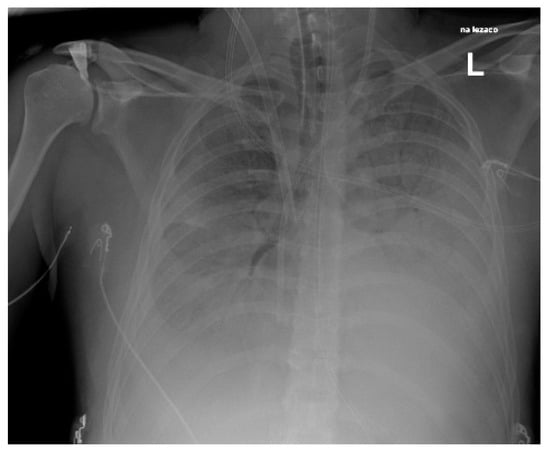

| 6 | 49/F | Pneumonia Pleural empyema | Type 2 Diabetes Mellitus | no | 9 | 3 | no | 58 days | Discharge |

| 6 | No | pleural drainage | pleural fluid | Ceftriaxone Metronidazole | Penicillin Clindamicin |